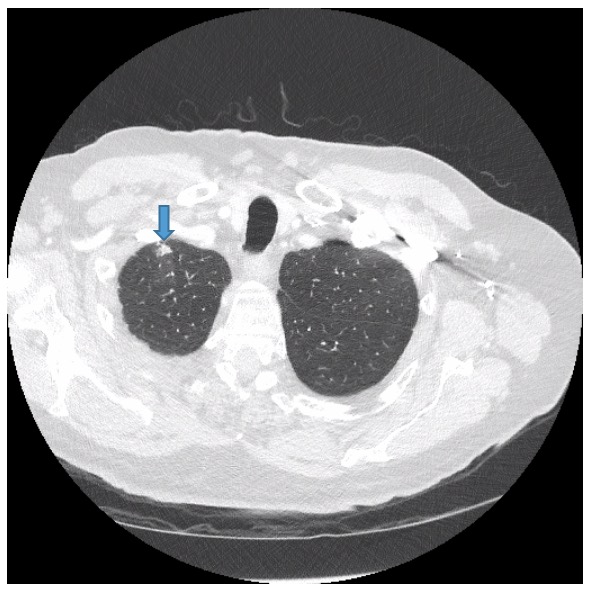

Diagnostic tests. Routine colonoscopy findings of the descending colon were unremarkable; however, the colonoscope could not be advanced in the transverse colon to the hepatic flexure. Consequently, CT colonography without contrast, more popularly referred to as virtual colonoscopy, was performed, the results of which showed eventration of the left hemidiaphragm with a large hiatal hernia containing transverse colon (Figure 1), as well as incidentally noted ill-defined nodular opacities within the right upper lobe with concomitant ground-glass attenuation (Figure 2).

Figure 2. Also noted incidentally on virtual CT were ill-defined nodular opacities within the right upper lobe with concomitant ground-glass attenuation.

Contrast-enhanced chest CT scans showed a 1-cm nodular opacity (Figure 4) and a 1.6-cm subpleural nodular opacity (Figure 5) within the apical segment of the right upper lobe, and ill-defined ground-glass opacity within the posterior segment of the right upper lobe (Figure 6).

Figure 4. Contrast-enhanced chest CT showed a 1-cm nodular opacity in the apical segment of the right upper lobe.

Figure 5. Contrast-enhanced chest CT showed a 1.6-cm subpleural nodular opacity within the apical segment of the right upper lobe.

Figure 6. Contrast-enhanced chest CT showed ill-defined ground-glass opacity within the posterior segment of the right upper lobe.

The impression was right upper lobe nodular opacities for which 3-month follow-up would be recommended.